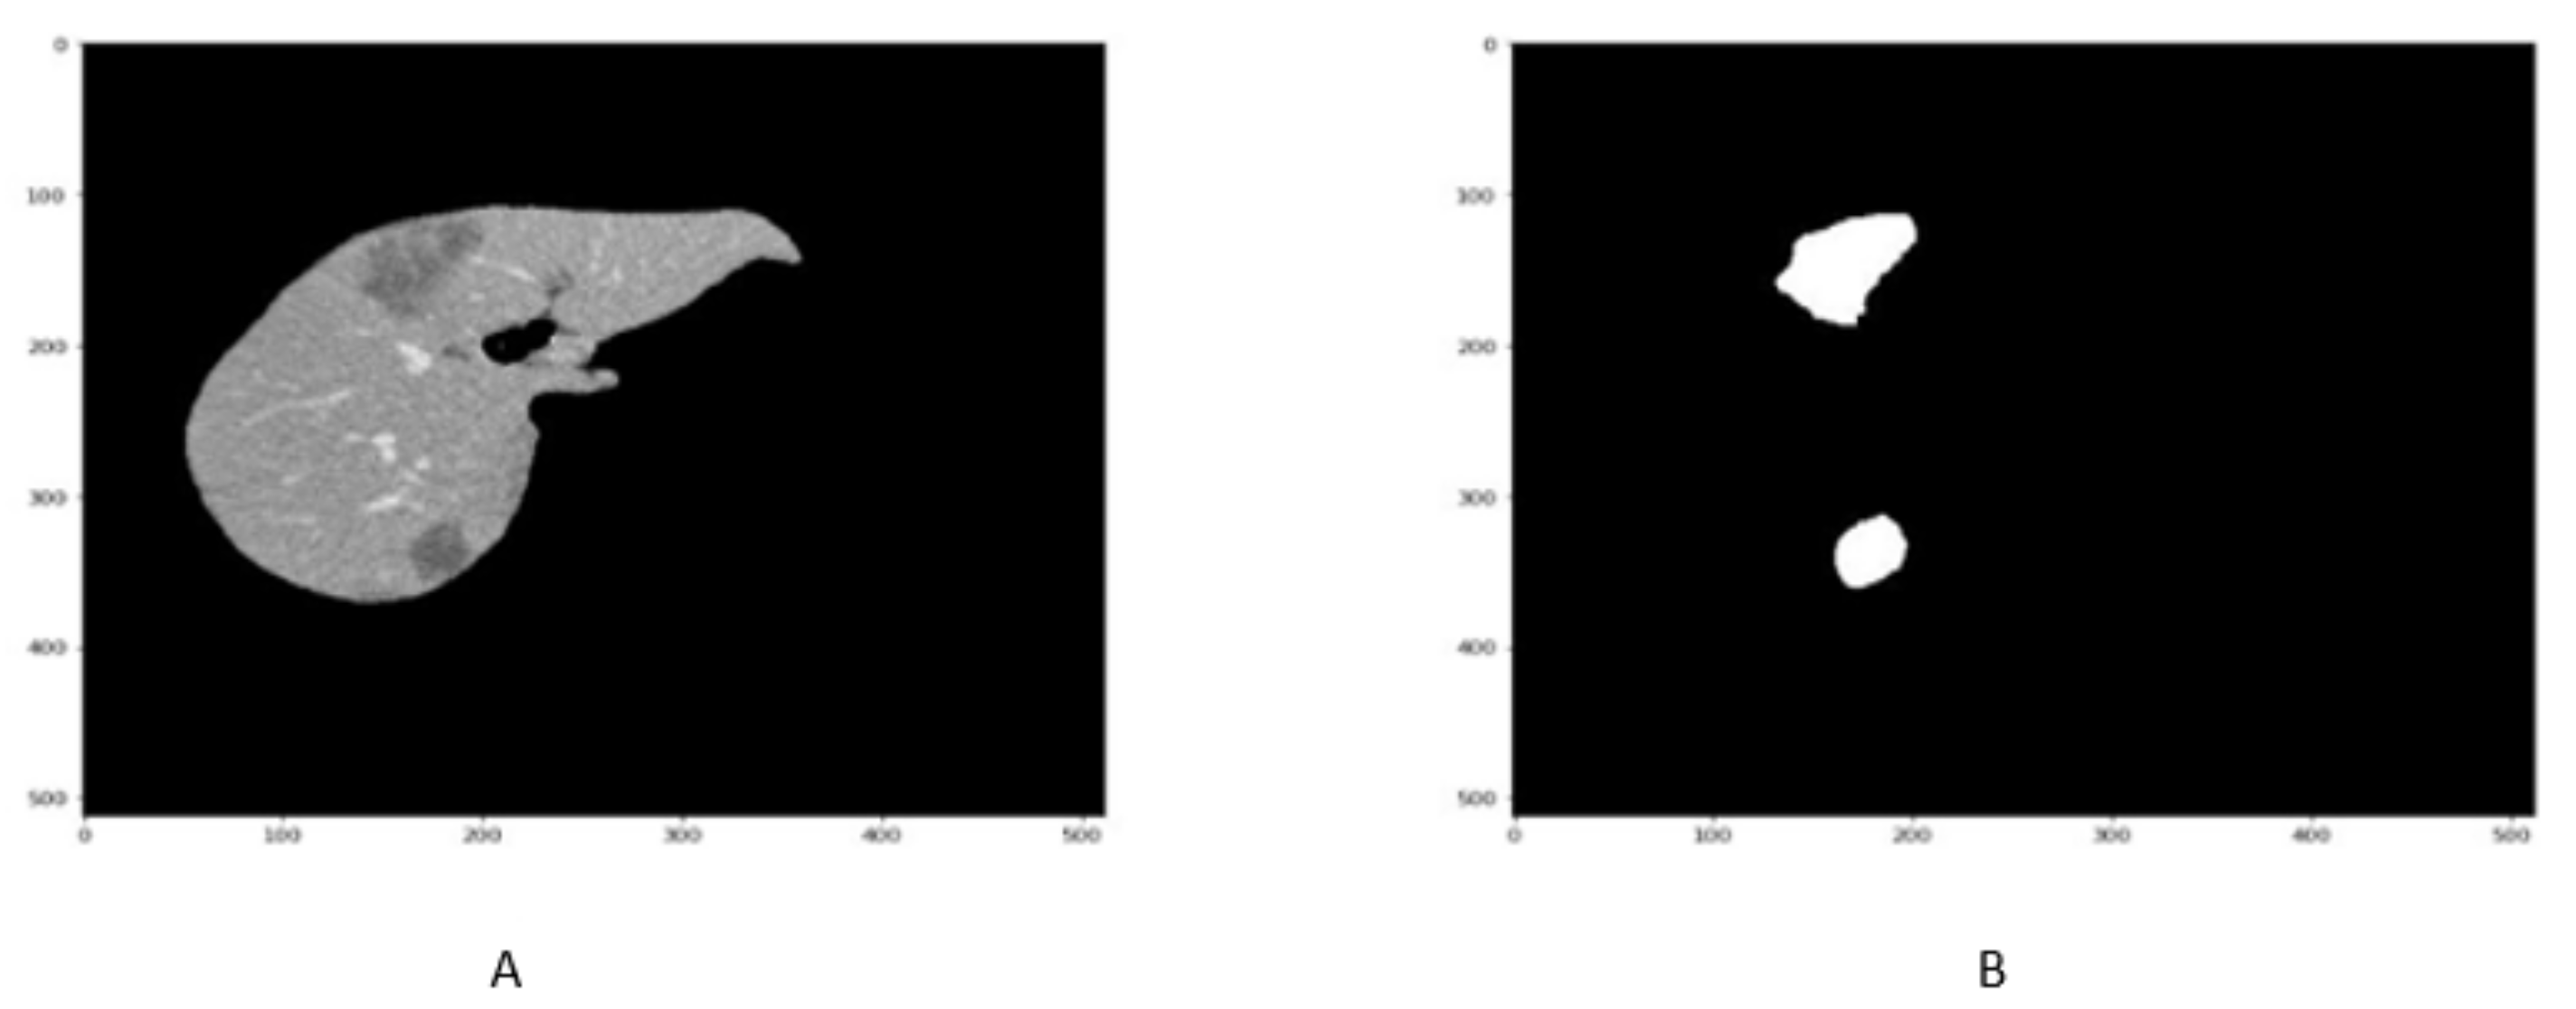

In order to enhance the visualization of the liver, HU windowing is performed at each slice where the HU range of −100 to 400 is selected, as shown in Figure 2. It shows that most organs are occluded in CT image slices without windowing operation, while the image and organs became clearer after HU windowing. Therefore, this HU windowing is performed over all slices before passing them to the next process.

Figure 2.

Figure represents the HU windoing results in (A,B), While Figures (C,D) shows the HU windowing results not having Liver.

Although HU windowing provides good visualization of organs, it was still difficult to differentiate between the liver and adjacent tissues. Therefore, histogram equalization was applied to the image obtained after window processing and then normalized in the range of [0, 1] as shown in Figure 3. It can be seen that as compared with Figure 2A,B, the organs boundaries are more evident in Figure 3C,D after histogram equalization.

Figure 3.

Figure shows that the CT slice (A,B) before histogram equalization, While CT slice (C,D) after histogram equalization.